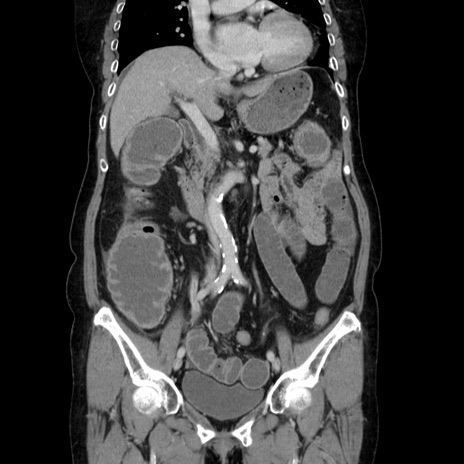

症例5(冠状断像)

【症例】70歳代女性

【主訴】お腹が張る

【現病歴】1週間くらい前から腹部膨満の自覚あり。昨日夜から増悪したため、本日救急外来受診。

【身体所見】意識清明、BT 36.5℃、BP 165/106mmHg、HR 80bpm、SpO2 98%、腹部:膨満、軟、自発痛・圧痛なし、触診にて不快感あり、腸蠕動音:減弱

【データ】WBC 12600、CRP 1.04

横断像